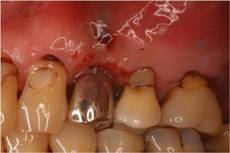

インプラント周囲炎

Perio Wave+Er:YAGレーザー+コールドレーザーの例です。

左の画像が照射前です。3ヶ月でここまで治癒しました。